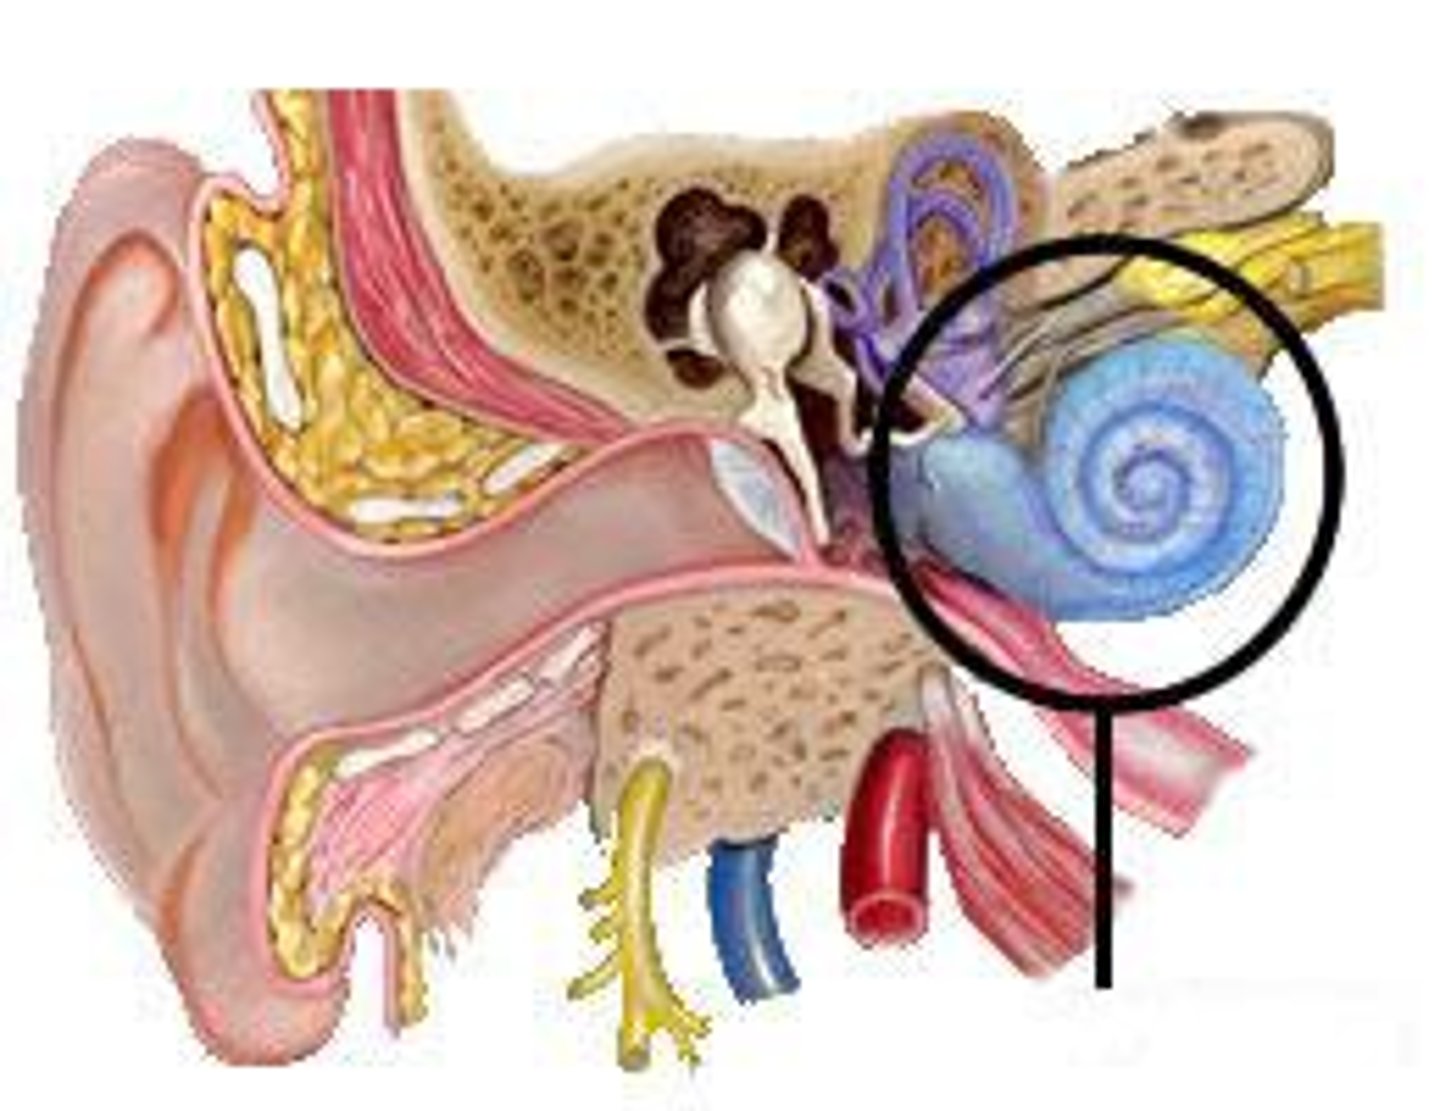

auditory ossicles

tympanic membrane

tympanic cavity

Eustachian tube

mastoid air cells

coclea

semicircular canals